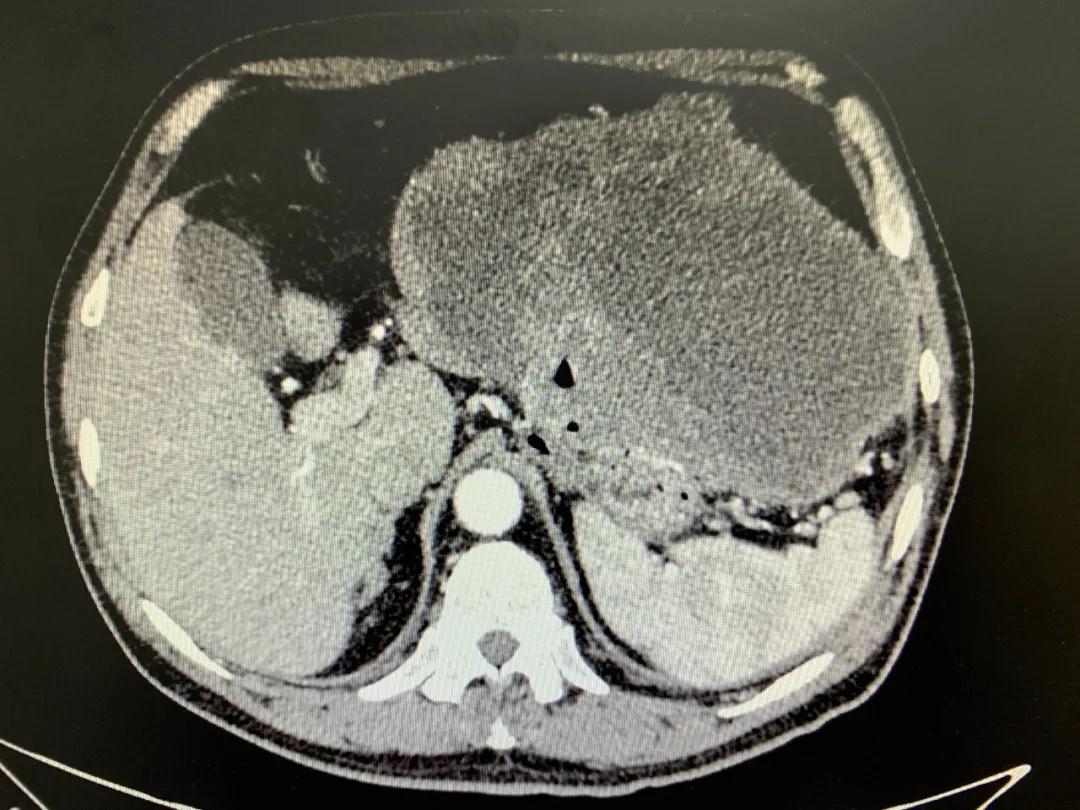

患者入院時血紅蛋白數(shù)值仍持續(xù)下降,出現(xiàn)失血性休克表現(xiàn),危及生命。消化外科二病區(qū)蔡磊主任接診后,組織科室迅速對患者進行了全面的檢查。CT提示腫瘤大小約19.3*10.3cm,腫瘤內提示大量積血。結合相關檢查,考慮為罕見的巨大胃間質瘤合并出血。